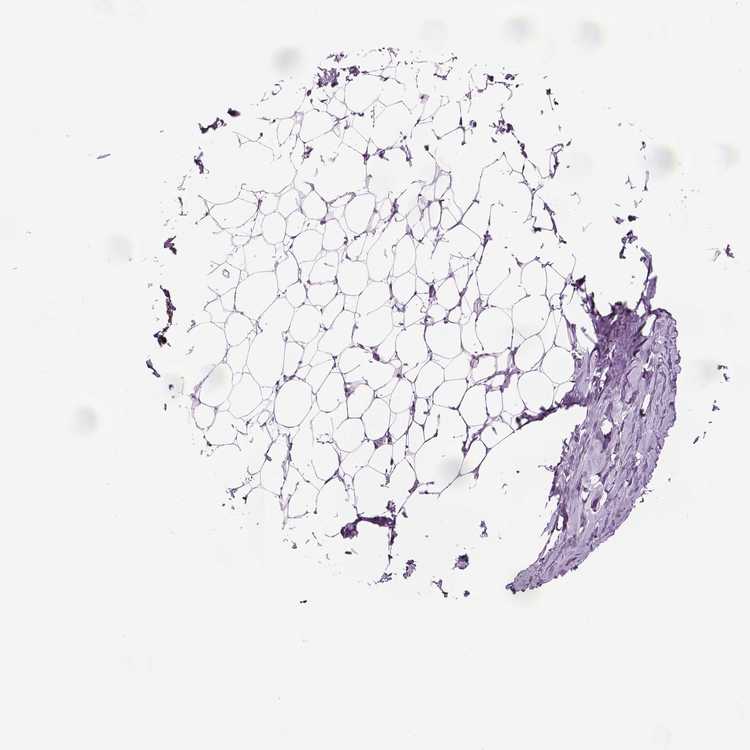

BREAST - Antibody stainingi

Antibody staining in the annotated cell types in the current human tissue is reported as not detected, low, medium, or high, based on conventional immunohistochemistry profiling in selected tissues. This score is based on the combination of the staining intensity and fraction of stained cells.

Each image is clickable and will lead to virtual microscopy that enables deeper exploration of all samples and also displays staining intensity scores, fraction scores and subcellular localization as well as patient and tissue information for each sample.

Antibody HPA045904

Adipocytes Not detected

Glandular cells Not detected

Myoepithelial cells Not detected